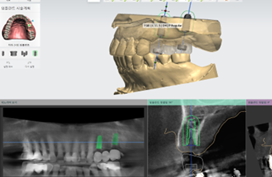

컴퓨터 분석 임플란트

3D 모의수술을 통한 정확성 UP!

3D CT, 구강 스캐너 등 디지털 정밀 진단을 접목한 모의 수술로 사전에 잇몸뼈, 신경, 보철 등을

모두 고려하여 식립 위치를 결정하여 개개인에게 맞는 수술 유도 장치를 제작하는 방법입니다.DIGITAL IMPLANT

컴퓨터 분석 임플란트 수술을 위한 가이드를 원장이 직접 디자인하고 제작합니다.